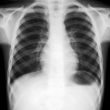

Ellis-Van Creveld Syndrome

Ellis-van Creveld (EVC) syndrome is one form of the ectodermal dysplasias, a group of disorders that affect the embryonic ectoderm, which is the outer layer of the developing embryo. The ectodermal layer develops into many parts of a baby's body, including... read more